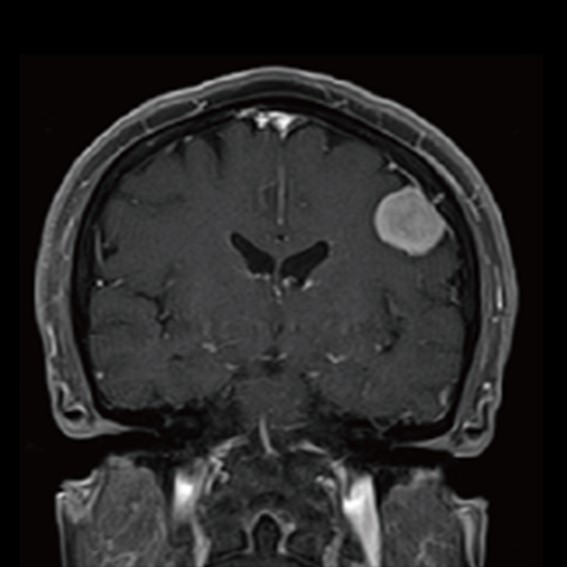

運用高科技尖端影像設備,提供貴賓精準的檢查、判讀、即時醫療、後續追蹤、健康管理或醫學中心轉介服務;從健檢診斷到後端治療,一條龍式服務。永越自成立以來,已服務超過16萬人次,每年通報件數超過千件,揪出包括:甲狀腺癌、肝腫瘤、肺癌、乳癌、子宮頸癌等重大異常的健康警訊,把握住早發現早治療的黃金關鍵。